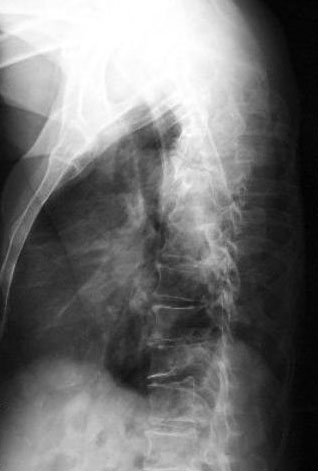

Osteoporosis. Cifosis.